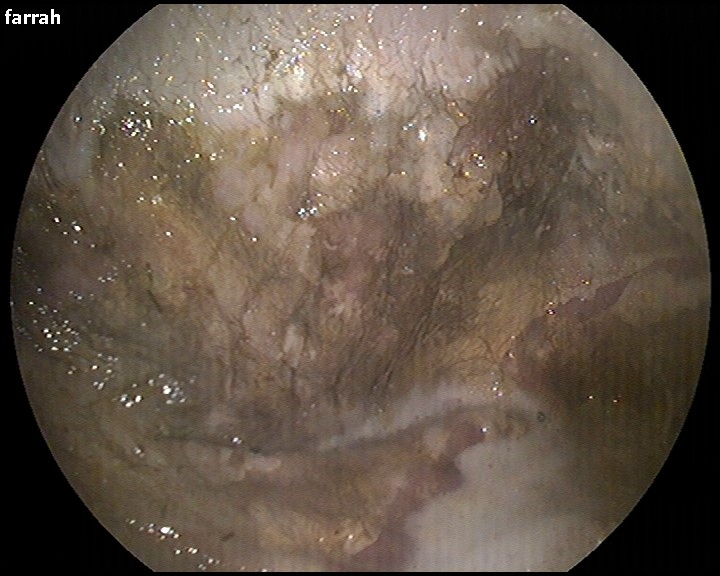

Figure 3: gastric ulceration is a common development following ingestion of blister beetles. A) demonstrates a healthy stomach the upper light colored area and lower pink areas are normal components of the gastric lining in horses, whereas B) reveals the changes that can be seen in association with cantharidin toxicity. The horse in panel B has loss of the normal light colored (squamous) area which has suffered from extensive ulceration.

In horses that experience clinical signs of toxicity, severe gastric ulceration and electrolyte abnormalities may occur (Figure 3). Blood testing can determine a very low calcium concentration which can cause a condition known as “thumps” also called synchronous diaphragmatic flutter (SDF). Synchronous diaphragmatic flutter occurs when electrolyte levels are at a dangerously low concentration, most commonly associated with low calcium levels.